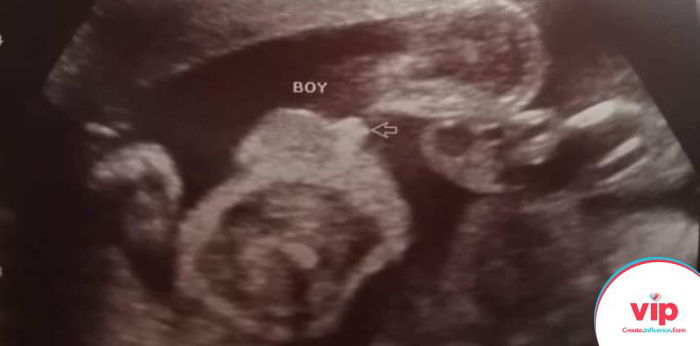

Hello mga mommies! Meet my bebe boy, we named him Khairo. Still preggy ako as of now (team November here) and first-time mommy din ako.

I was 20 weeks pregnant nung first ultrasound ko and dun ko lang nalaman na preggy ako at may low lying with subchorionic hemorrhage pa.

Sa awa naman ni Lord tsaka sa pagtatiyaga ko na mag-bedrest kahit ang sakit na sa likod, now i’m 8 months preggy. Cephalic na siya, kumakapit at healthy ang baby boy ko and finally, high lying na ko so pwede na ko mag-normal delivery.